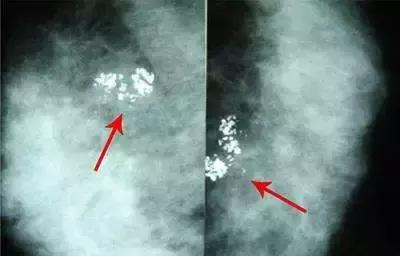

6、钙化

钙化在乳腺片子里是非常常见的,有问题的恶性“钙化”是非常少见的。散在点状的、孤立的、大的、圆圆的钙化其实都是良性的钙化,虽然一旦产生就不会消失,但终生也不会恶变,也不需要管它。不过,可疑恶性的钙化一定需要医师进一步的处理。